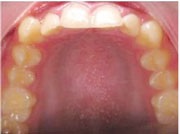

Figs. 3a-g: Initial records.

Fig. 3a

Fig. 3b

Fig. 3c

Fig. 3d

Fig. 3e

Fig. 3f

Fig. 3g